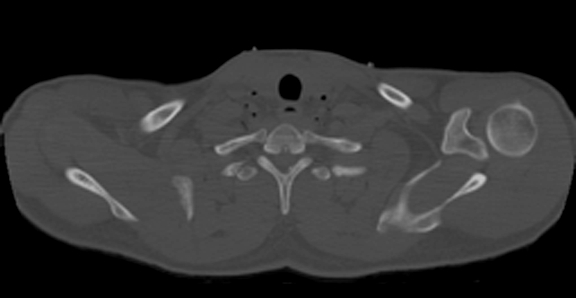

• Horizontal CT Section at this level